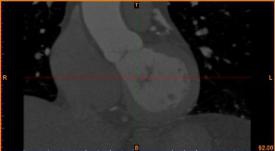

病例描述:

病人患冠心病,堵塞處較多,決定采用搭橋治療。

醫(yī)生需求:

需要準(zhǔn)確定位病灶位置,加快手術(shù)時(shí)間。

建模過程:

首先通過病人的心臟冠脈造影CT數(shù)據(jù),獲取病人的心臟冠脈三維模型。

病人的冠脈造影CT數(shù)據(jù)                                              提取出的冠脈三維數(shù)據(jù)

其次在對(duì)應(yīng)的病灶位置進(jìn)行一定的細(xì)節(jié)修改,或改變其形狀或改變顏色以便于突出顯示病灶位置。

模型細(xì)節(jié)修改

模型打?。?/strong>

最后為方便醫(yī)生觀察病灶以及模擬手術(shù),給整個(gè)冠脈模型添加支撐和底座,之后通過3D打印技術(shù)制作出來。

給冠脈模型添加支撐和底座并打印出來

適用科室:

心血管科、外科、周圍血管科